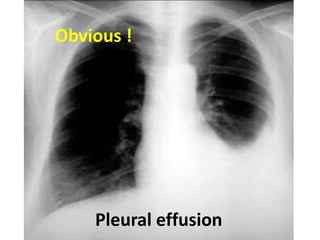

Pleural effusion

Obvious !